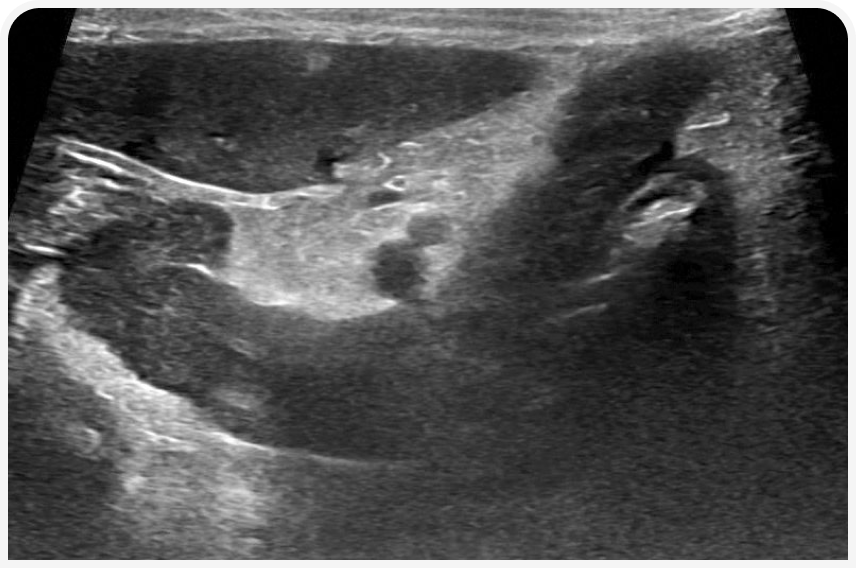

По мнению автора, у кошки с потерей веса невыясненного происхождения часто очень информативным для диагностики оказывается ультразвуковое исследование органов брюшной полости. Особенно внимательно исследуют желудочно-кишечный тракт, определяя общую толщину стенки различных отделов кишечника и соотношение толщины слизистой оболочки и мышечного слоя. Как правило, требуется дообследование любых сегментов тонкой кишки с толщиной стенки > 3 мм; на патологию также может указывать увеличение толщины мышечного слоя (19). Диффузное утолщение мышечного слоя иногда наблюдается у клинически здоровых кошек, но чаще — при ВЗК или инфильтративных заболеваниях желудочно-кишечного тракта, таких как мелкоклеточная лимфома и гистоплазмоз (Рисунок 3).

Ультразвуковое исследование позволяет обнаружить и другие проявляющиеся только незначительным дискомфортом и вызывающие вторичную гипорексию поражения органов брюшной области, такие как хронический панкреатит, хотя подобные малозаметные изменения эхогенности трудно оценить корректно, не имея высококачественного аппарата или значительного опыта специалиста (Рисунок 4) (16). При ультразвуковом исследовании легко выявить поражения почек (например, обструкцию мочеточника или гидронефроз), нередко вызывающие хронический дискомфорт, достаточно выраженный, чтобы нарушить потребление пищи (20). Если контралатеральная почка не поражена, уровень креатинина в сыворотке крови и удельный вес мочи будут находиться в пределах референсного интервала.